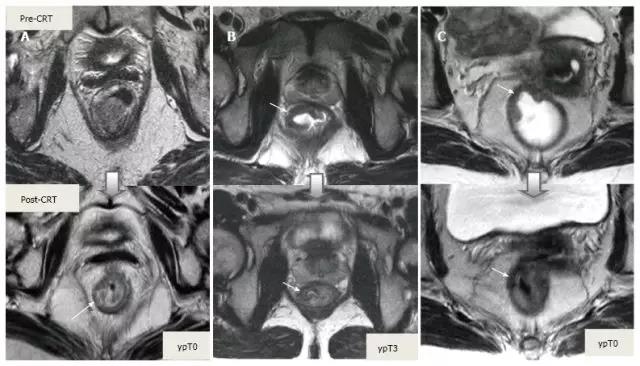

采用传统 MRI 序列对 CRT 后肿瘤重新分期的精确性差于初始分期,尤其在证实完全缓解(yT0),主要是很难将残留的肿瘤与纤维化、水肿和正常粘膜区分开,因此 CRT 后正常的 2 层直肠壁提示为完全缓解,而残留纤维化既可以是肿瘤残留也可以是完全缓解(图 17)。

实际上 CRT 后 T2 加权 MRI 后上纤维化的信号强度很低,而残留肿瘤区域则为中等强度,仔细评估高分辨图像和 DWI 是能区分小的残留病变和纤维化的(图 18)。

图 17. 新辅助放化疗后肿瘤重新分期。在不同患者的 T2 加权 MR 图像上分别显示(上:治疗前,下:治疗后)。A. 在 ypT0 直肠肿瘤中,治疗后的轴位图像显示正常的两层直肠壁(箭头),对应完全缓解;B. 在 ypT3 直肠肿瘤中,治疗后的轴位图像显示正常的双层直肠壁(箭头)。这是 MR 评估完全缓解的假阴性例子;C. 在 ypT0 直肠肿瘤中,原有肿瘤区域治疗后呈现厚的、纤维化的低信号强度疤痕(箭头)。